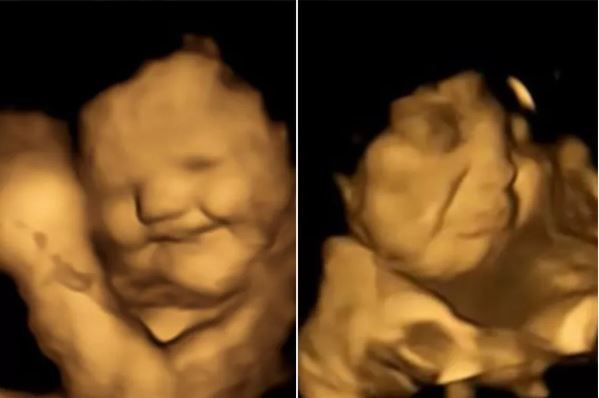

Links die lachende Reaktion nach Karotten, rechts der Schmollmund nach Kohl.

FETAL AND NEONATAL RESEARCH LAB/DURHAM UNIVERSITY